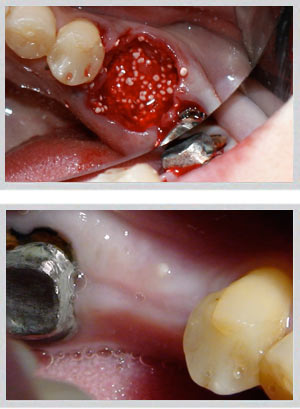

Upper jaw: GBR (guided bone regeneration) for moderate buccal defects; block bone grafting for larger volume requirements. Socket preservation at time of extraction prevents bone loss from occurring in the first place.

Lower jaw: Block bone grafting for severe buccal wall defects. Easy Graft Crystal (non-resorbable beta-tricalcium phosphate) for minor to moderate deficiencies. Socket preservation equally critical.

Dr. Zarifeh's preferred protocol combines synthetic Easy Graft with autogenous bone chips — pairing the structural scaffold of a synthetic material with the biological activity of the patient's own cells. The selection is made individually per case based on defect size, location, and planned implant timeline.